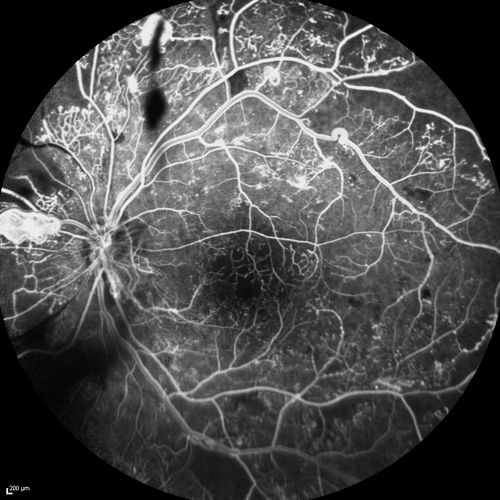

Proliferative Diabetic Retinopathy - Moderate - mild NVD with NVE

FA shows leakage from neovascularization and dark areas in periphery from non-perfusion